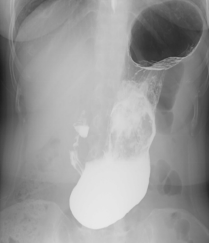

如果您最近吃了大量的柿子、山楂、黑枣、石榴等,又出现上述症状,请前往正规医院行钡餐、 CT 或胃镜检查。

上消化道钡餐检查